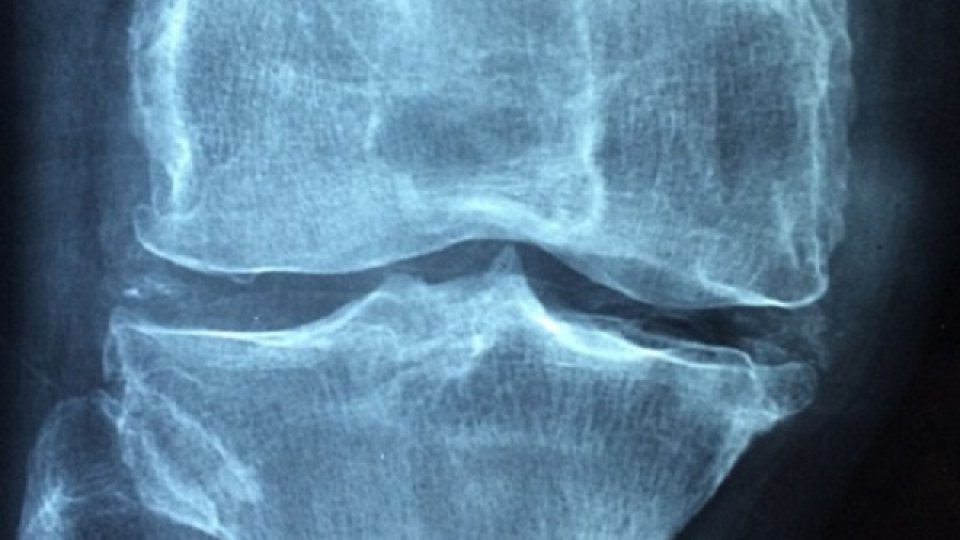

Osteoartrita: ce tratamente sunt recomandate?

Osteoartrita este uzura articulațiilor. Este foarte frecvent, chiar omniprezent odată cu vârsta, deoarece de la 75 de ani, 70 până la 90% dintre oameni o au.